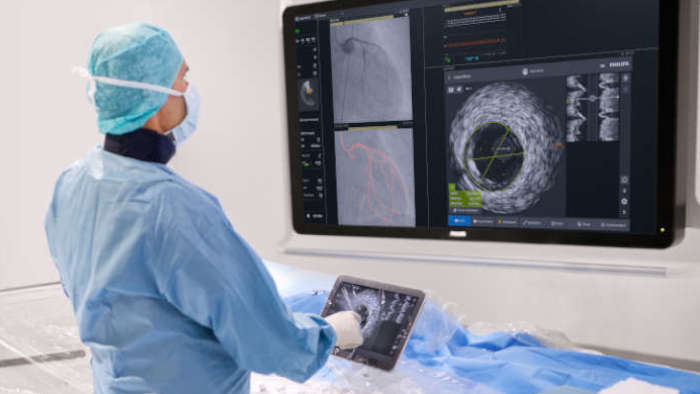

A medida que aumenta el número de pacientes cardiovasculares y vasculares, también lo hace la necesidad de trabajar de forma más inteligente y rápida. Philips IntraSight le ofrece estas herramientas intervencionistas, las mejores de su clase, que le permiten ver con claridad para poder tomar decisiones clínicas rápidas e informadas que pueden conducir a planes de tratamiento óptimos. La integración de la más avanzada plataforma de fisiología e imagenología en su flujo de trabajo debe ser inteligente, sencilla y constante. IntraSight es la única plataforma intervencionista que: Para los clientes con suites intervencionistas que no son de Philips, IntraSight 7 ofrece una integración constante y un uso completo de nuestras aplicaciones de intervención. IntraSight 7 promueve una gestión mejorada del flujo de trabajo con el módulo de pantalla táctil junto a la mesa que permite la facilidad de uso y el acceso a las mejores herramientas intervencionistas de su clase, como iFR/FFR, IVUS y el corregistro. Además, la integración de IntraSight 7 con las suites intervencionistas que no son de Philips permite a los clientes beneficiarse de soluciones intuitivas como, por ejemplo, la mejora de los vasos y la detección de dispositivos, lo que, en última instancia, permite a todos los clientes beneficiarse de la oferta integral de soluciones inteligentes de IntraSight 7 sin compromiso.

Presentamos la nueva plataforma de aplicaciones intervencionistas Philips IntraSight, en la que la imagen, la fisiología, el corregistro* y el software se unen para facilitar una atención óptima del paciente. IntraSight ofrece un conjunto completo de modalidades clínicamente probadas, como la iFR/FFR, la IVUS y el corregistro* para simplificar las intervenciones complejas, acelerar los procedimientos rutinarios y proporcionar una mejor atención al paciente.

IntraSight está perfectamente integrada

Optimización del rendimiento del laboratorio con control de pantalla táctil en la mesa, integración de sistemas, gestión de datos y diagnóstico de servicios remotos.